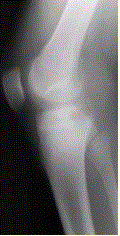

问题 患者男,15岁。右膝X线平片和CT检查见下图。 对于此病变的征象,描述不正确的是

选项 A.右胫骨内侧平台近关节面下不规则溶骨性破坏 B.边缘可见硬化缘 C.病灶内可见多发细小点状钙化 D.可见骨膜反应 E.病变为偏心性生长

答案 D